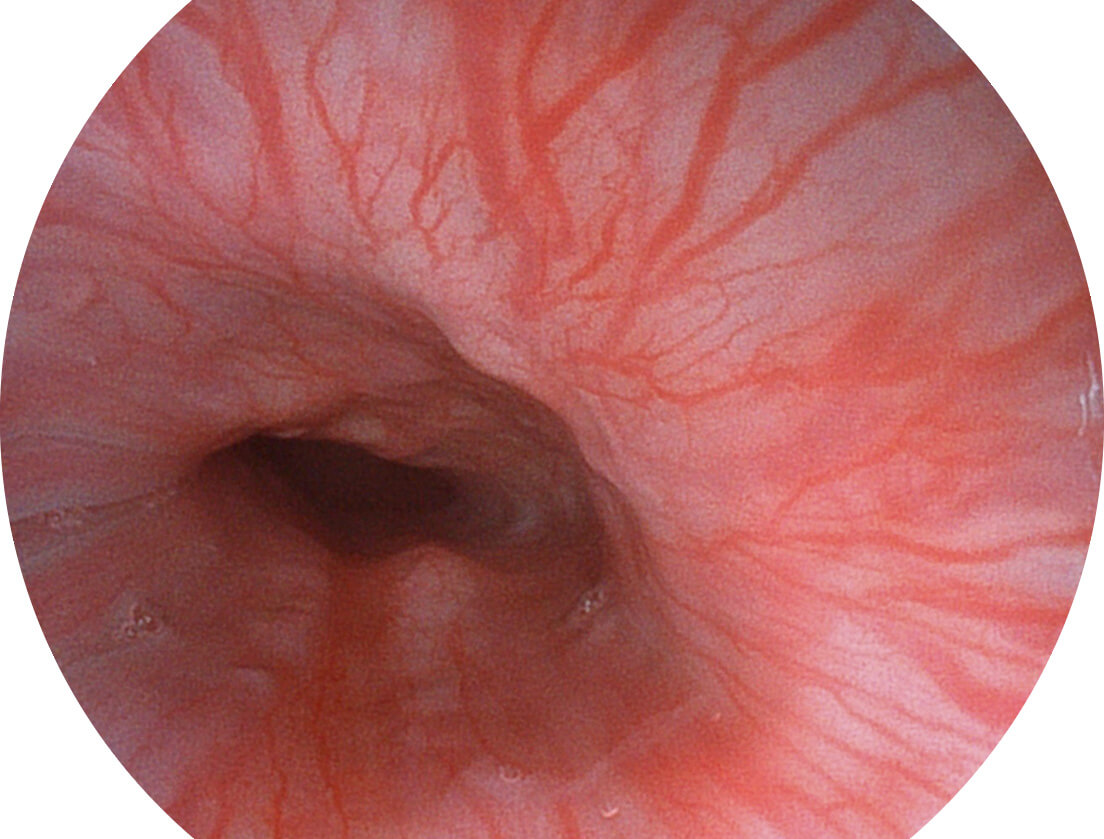

强调浅层黏膜结构的同时,保证照明亮度和提升浅层微血管与中层血管颜色对比度,病变边界更清晰。

VIST图像